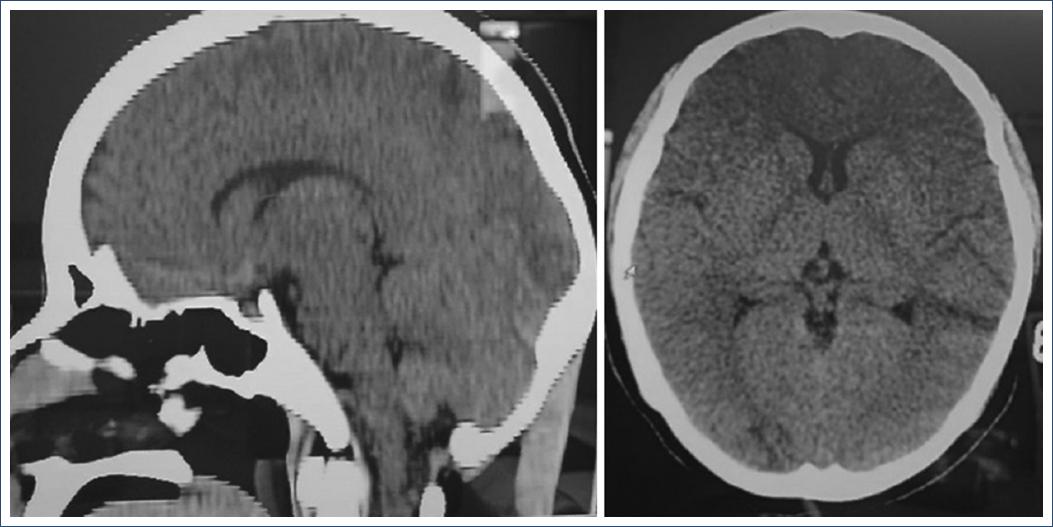

She underwent neurocritical care on the recommendation of the neurology service, with ICP monitoring inferred by optic nerve sheaths diameter measurement ICP 15-16 mmHg, remained under deep sedation after cesarean section for 48 h and subsequently emerged without data of delirium, without any manifestation of neurological deterioration. Tomographic: Areas compatible with subarachnoid hemorrhage of the right frontal region and on the free edge of the cerebellum tent on the right side, both not > 1 cm, rest of the study with cisterns of the base and subarachnoid space of the normal convexity, at the level of cerebral parenchyma basal ganglia with hypodense images in their entirety compatible with edema and subtotal deep venous circulation thrombosis (Fig. 1).

Figure 1 Cranial tomography on axial projection where hypodensity corresponding to the affected area is observed. Source: Clinical record.